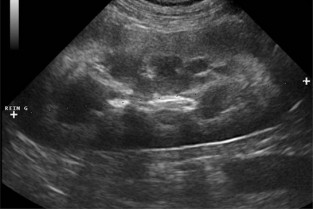

- Un temps d’exposés théoriques sur les principes physiques et contraintes techniques autorisant la reconnaissance des organes abdominaux, l’interprétation des artefacts et des images observées fréquemment chez l’animal sain ou présentant un état pathologique.

- Des travaux dirigés (sur vidéos) de reconnaissance d’images caractéristiques de processus pathologiques et de mise en situation de démarche clinique dans le cadre des modules de niveau avancé.

- lister les principales indications et les limites de l’échographie dans l’exploration de l’appareil urinaire et de l’appareil génital

- réaliser un examen échographique de l’appareil urinaire et de l’appareil génital

- interpréter les principales images anormales décrites pour ces deux appareils.